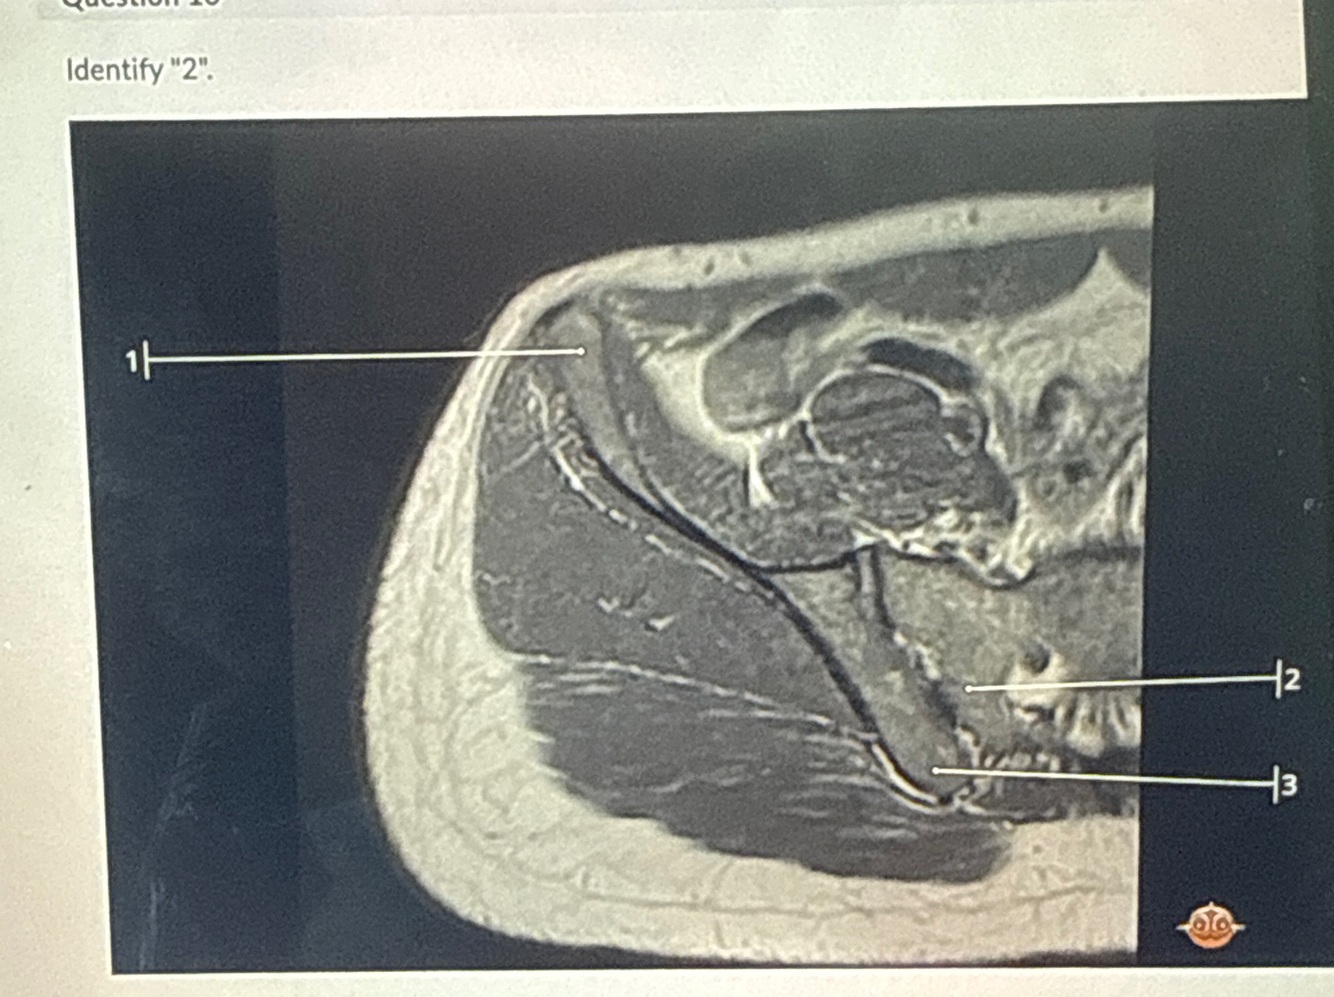

2

Q

A

D